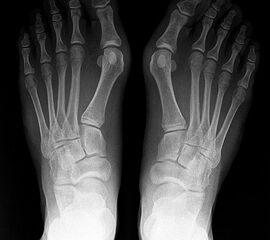

• Hallux valgus interphalangeus (Abb.1, Abb.2)

• Röntgenaufnahme des Fußes (unter Belastung) in dorsoplantarem und seitlichen Strahlengang (Abb. 2a-b).

• Beurteilung des proximalen Gelenkflächenwinkels der Grundphalanx (Proximal Phalangeal Articular Angle, PPAA) sowie des distalen Gelenkflächenwinkels der Grundphalanx (Distal Phalangeal Articular Angle, DPAA) 56 (Abb. 3c und 3d).

• Bestimmung des ersten Intermetatarsalwinkels (IMA, Abb. 3a), des Hallux valgus Winkels (HVA, Abb. 3a), des distalen metatarsalen Gelenskflächenwinkels (Distal Metatarsal Articular Angle, DMAA, Abb. 3b) 7. Möglicherweise muss die Akin-Osteotomie mit weiteren Eingriffen kombiniert werden (z.B.: retrokapitale Osteotomie oder andere metatarsale Osteotomie; Arthrodese).